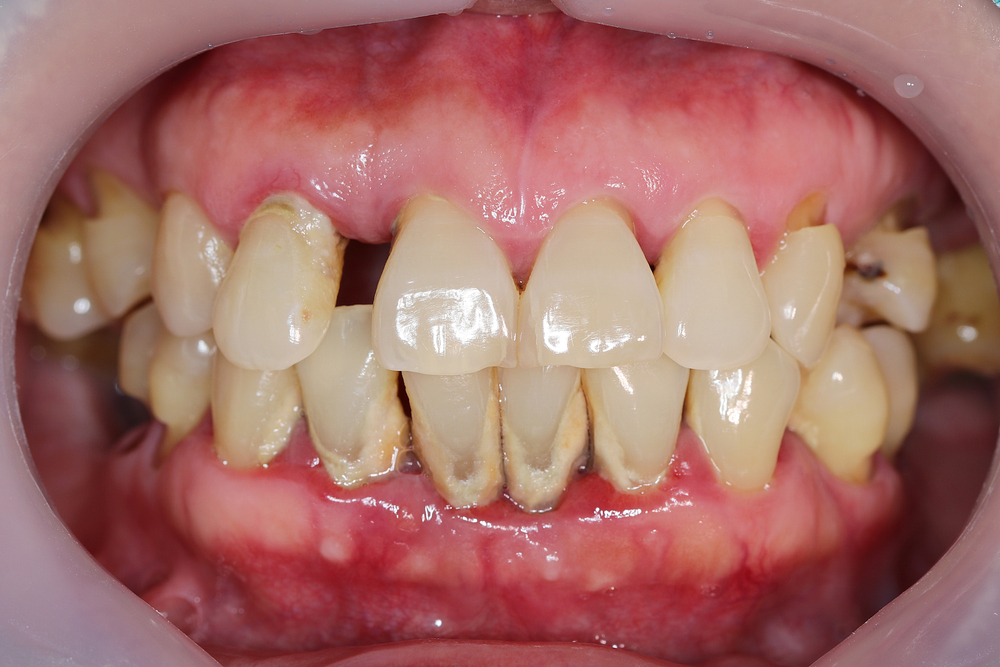

Diabetiker:innen haben ein dreimal höheres Risiko für eine Zahnfleischerkrankung als Gesunde. Betroffene können Zahnfleischentzündungen, Abzesse und Risse in den Mundwinkeln erleiden. Diese Symptome können zudem ein Hinweis auf einen unentdeckten Diabetes sein. Etwa ein Drittel aller Patient:innen wissen nichts von ihrer Erkrankung.

Ist die Insulinsekretion gestört, oder bereits eine Insulinresistenz bei den Zellen eingetreten, ist der Blutzuckerspiegel dauerhaft erhöht. Das führt wiederum zu einer höheren Anfälligkeit für Zahnfleischentzündungen. Das Immunsystem reagiert intensiver auf Zellgifte von Plaque-Bakterien am Zahnfleischrand. Veränderungen in den Gefäßwänden und Durchblutungsstörungen als Folge des Diabetes, erschweren es dem Körper zusätzlich, die Entzündungsprozesse zu kontrollieren. Liegt eine Parodontitis vor, so führt die Entzündung insgesamt dazu, dass Insulin noch schlechter wirken kann und der Diabetes sich verschlimmert. Es entsteht ein Teufelskreis, in dem sich beide Erkrankungen gegenseitig verstärken und das Risiko für weitere Folgeerkrankungen erhöht wird.

Deshalb ist es wichtig, eine effektive Parodontitis-Therapie durchzuführen und somit auch die Einstellung des Blutzuckerspiegels bei Typ-2-Diabetiker:innen zu verbessern. Eine gute Mundhygiene ist dabei Grundlage der Behandlung und unerlässlich. Da Parodontitis eine chronische Erkrankung ist, kann man sie nur stoppen, aber nicht gänzlich heilen. Mit der richtigen Behandlung kann ein Fortschreiten und der damit verbundene Zahnverlust verhindert werden – allerdings bedeutet das „lebenslänglich“. Betroffene sollten möglichst auf sehr kalte oder heiße und süße Speisen verzichten, da diese die offen liegenden Zahnhälse reizen. Durch die gelockerten Zähne können viele Patient:innen auch keine harten, zähen oder klebrigen Lebensmittel mehr genießen. Nach dem gründlichen Zähneputzen empfiehlt es sich, eine alkoholfreie Mundspülung zu benutzen. Die tägliche Reinigung der Zahnzwischenräume mit Zahnseide und Zahnzwischenraumbürstchen sollte in die Reinigungsroutine eingegliedert werden, um das Fortschreiten der Parodontitis zu vermeiden.